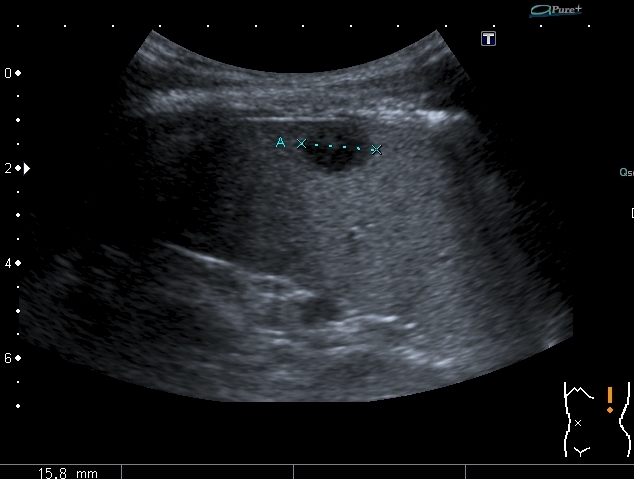

"Плохой"  подмышечный лимфатический узел, но справа. "Bad" axillar LN is seen

Hypoechoic lesions in the spleen. В селезёнке - множественные гипоэхогенные образования